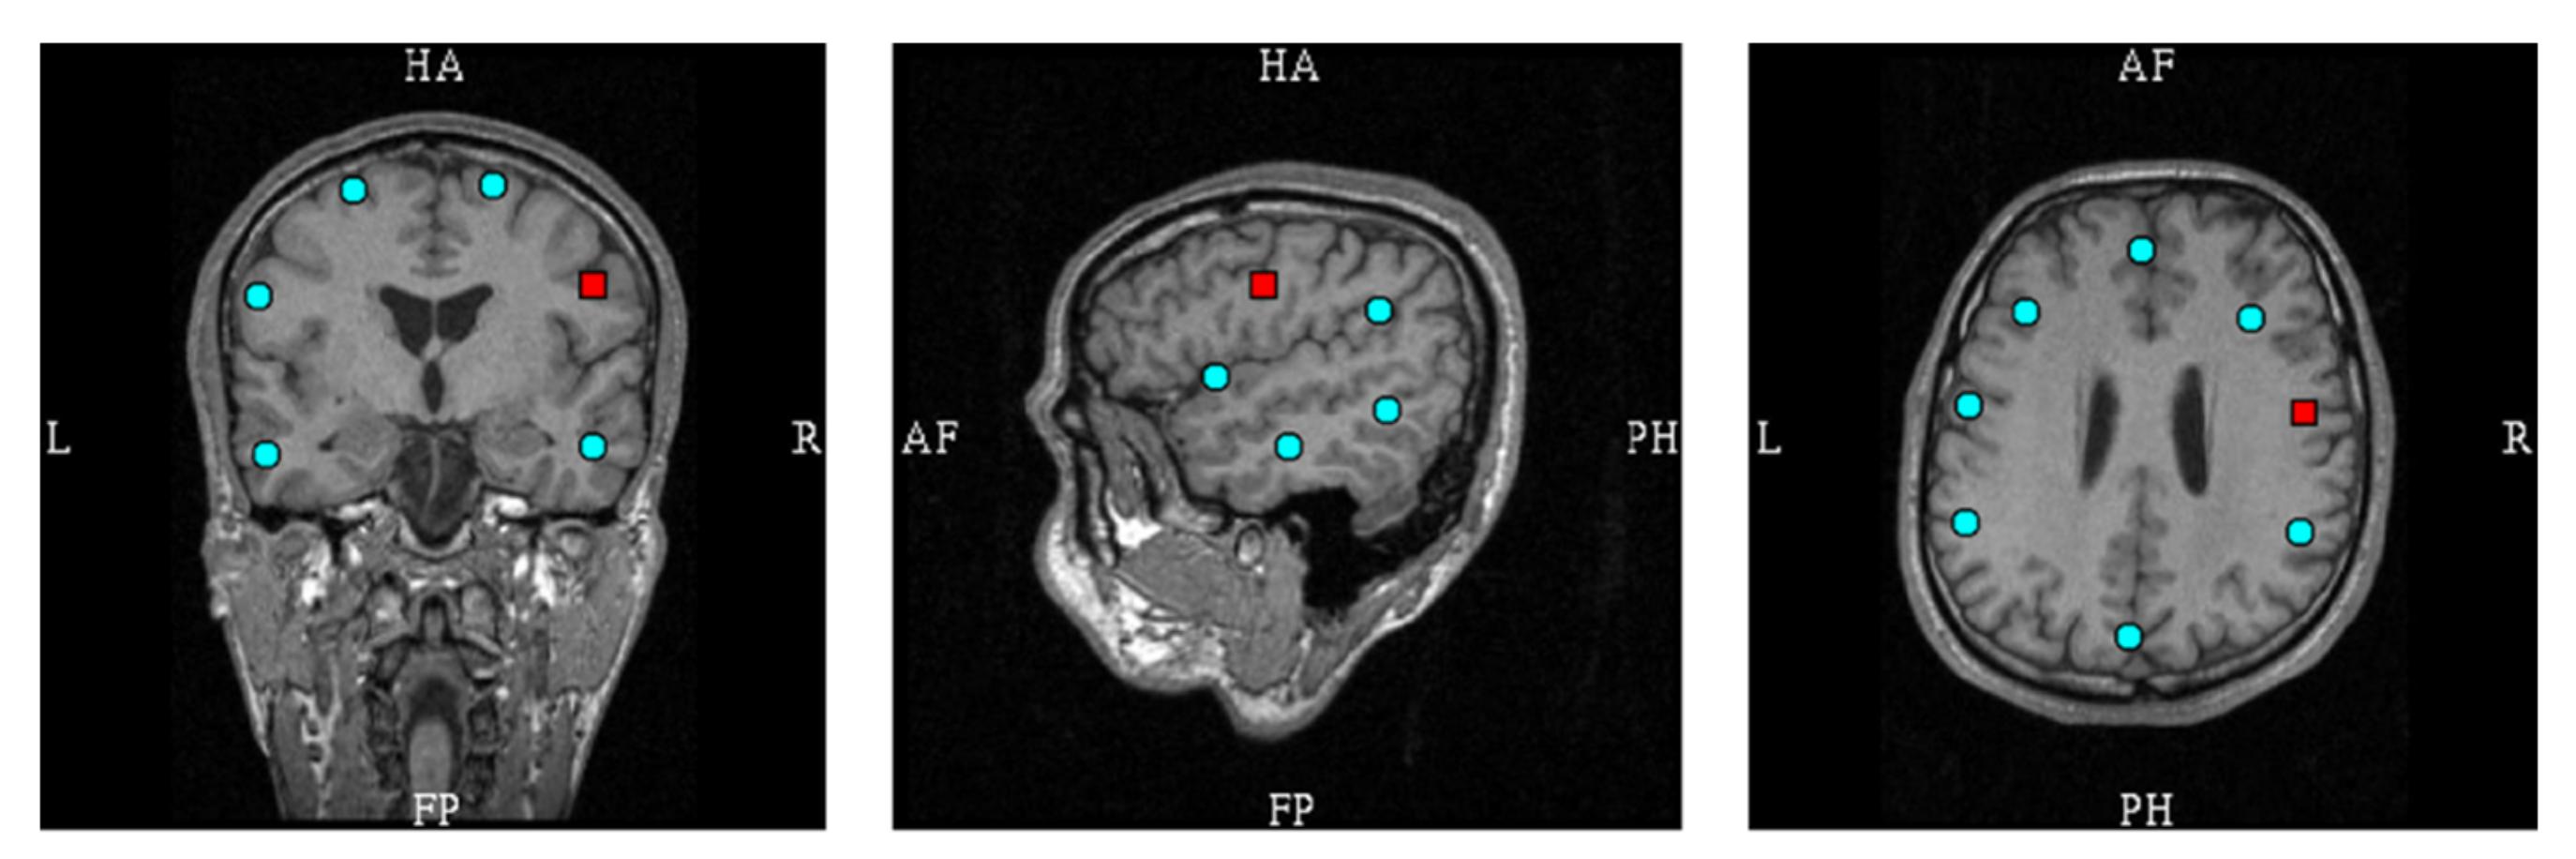

3.1. Source Dipoles at Montage Channel Locations